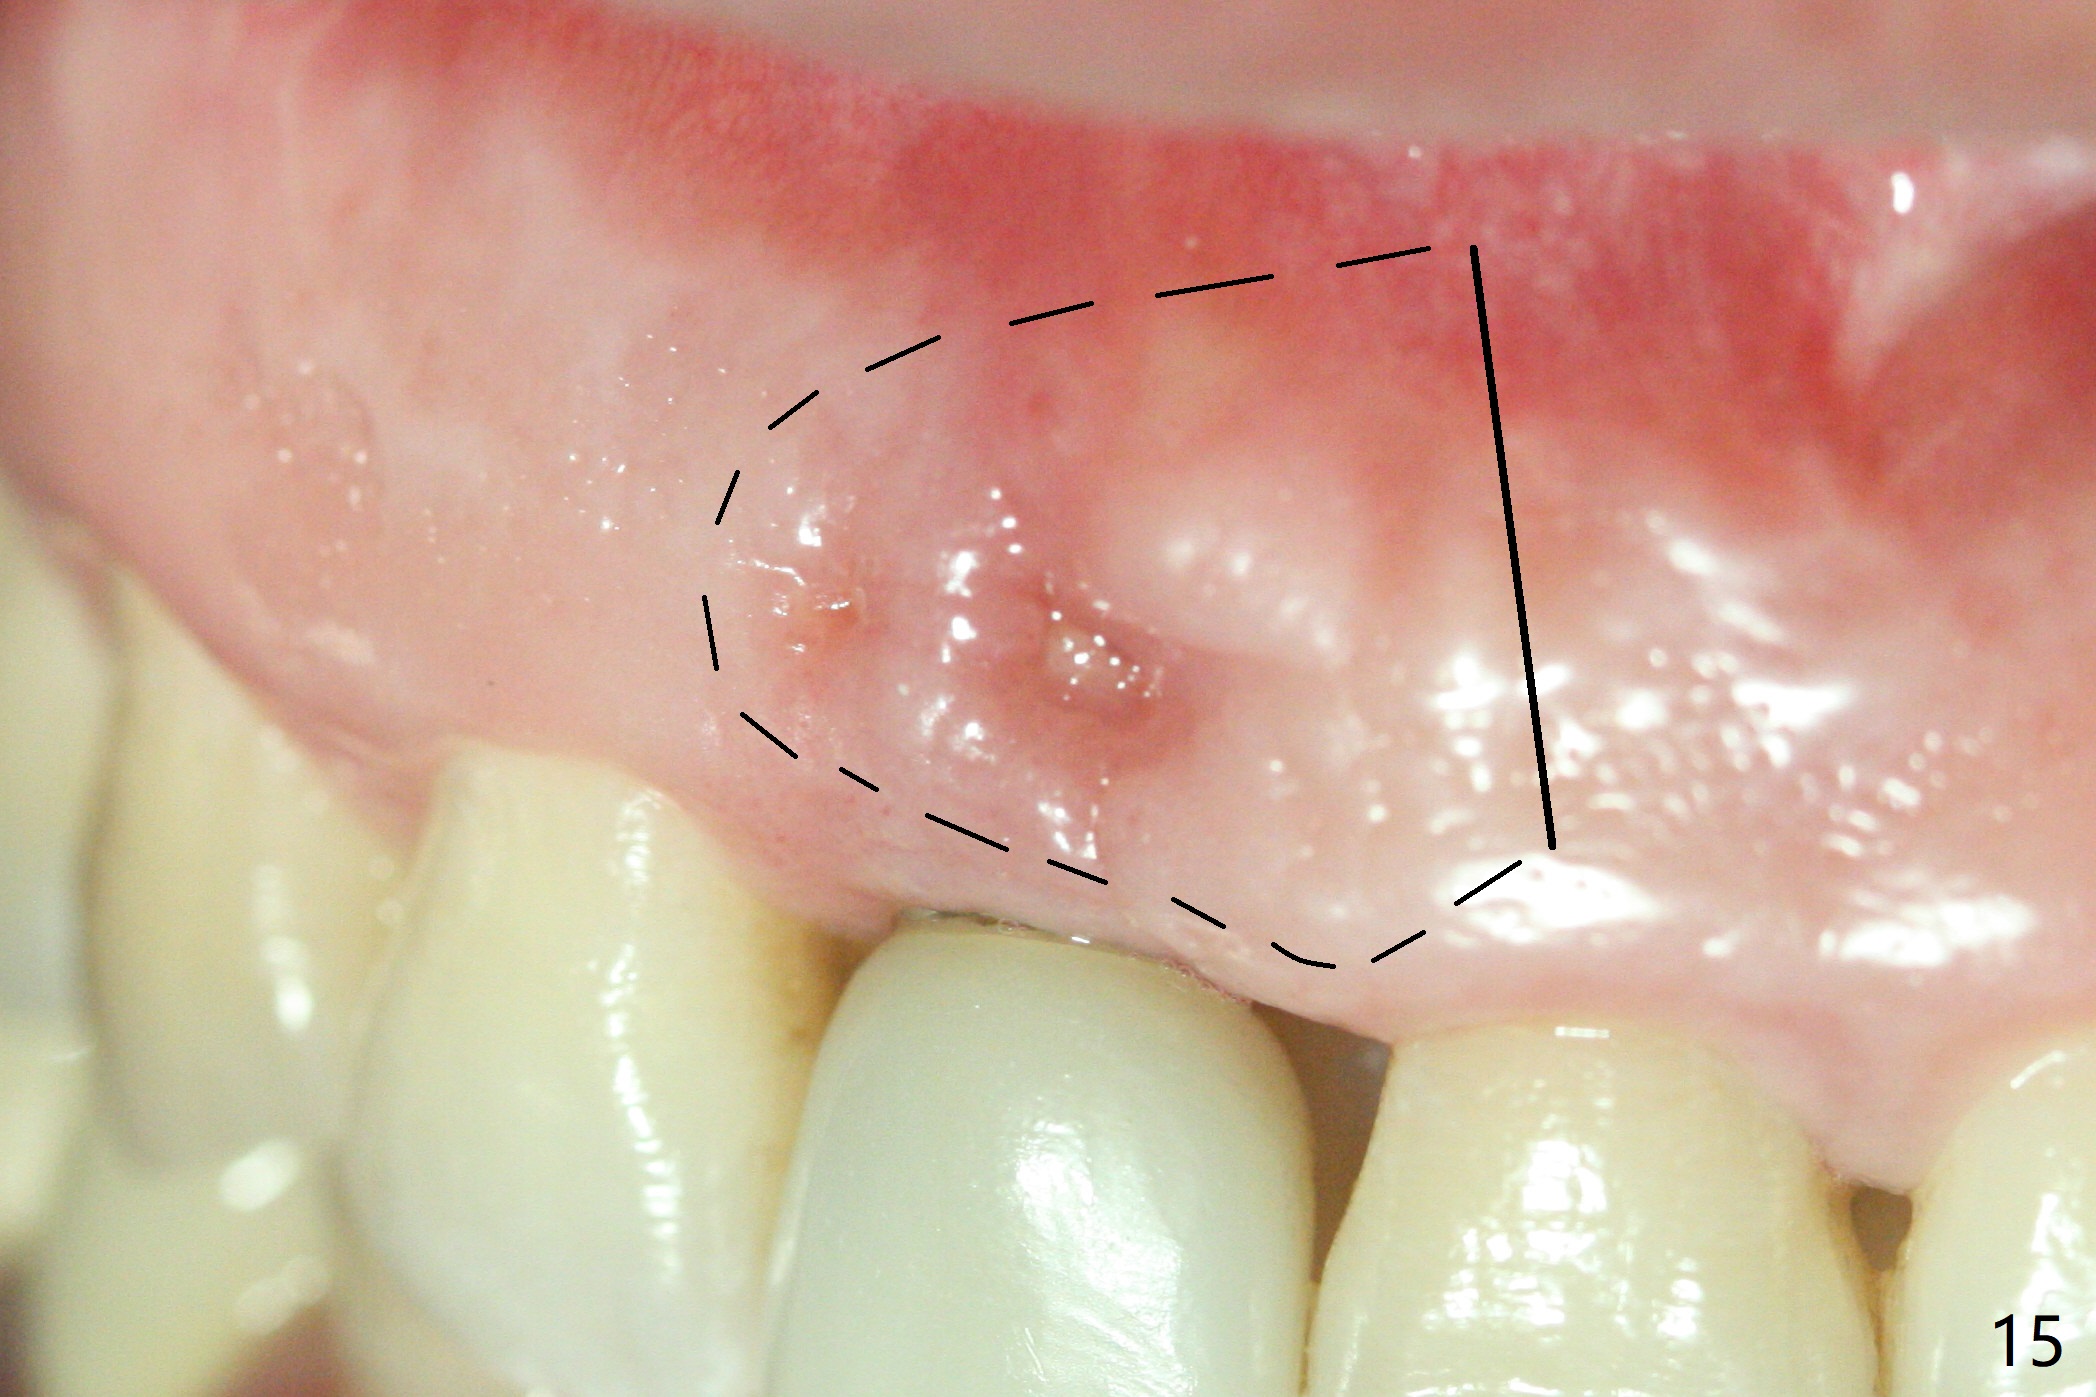

The patient returns because of purulent exudate from the buccal fistula (Fig.1 *) 1 year 9 months postop (1 year 3 months post cementation). Preop CT shows buccal thread exposure (Fig.2 arrowheads). To prevent postop gingival recession, a semilunar incision is made between the fistula and the gingival margin (Fig.3). After removal of granulation tissue (Fig.4), allograft in sticky bone form is packed (Fig.5). Following placement of PRF membrane and 6-month collagen membrane, the wound is closed (Fig.6). Since the implant (Fig.7 I) thread exposure is within bone (B) boundary (Fig.8 red dashed line), bone graft with PRF should be able to take care of periimplantitis (A: abutment). To prevent periimplantitis in similar situation, the immediate implant should be placed deep (not necessarily long, 18 mm) and narrower (3.5 mm instead of 3.8 mm). The defective buccal plate should be repaired with sticky bone and collagen membrane with incision if necessary. The wound does not dehisce 1 week postop (Fig.9) or 3 weeks postop (Fig.10, immediately post suture removal). Although bone graft seems to stay in place 6 months postop (Fig.11,12), the patient complains of bone graft expulsion sometimes. The buccal gingiva has deficiency (Fig.13). To fix it, make a remote incision (Fig.14 black line) and dissect before gingiva graft (Fig.15 dashed line). After removal of crown/abutment, the sinus track and implant surface are treated with Waterlase. A shorter cuff abutment is placed (4.5x5(4 to 3) mm) with a new provisional. The patient feels better with reduced sinus track 2 weeks postop (Fig.16).